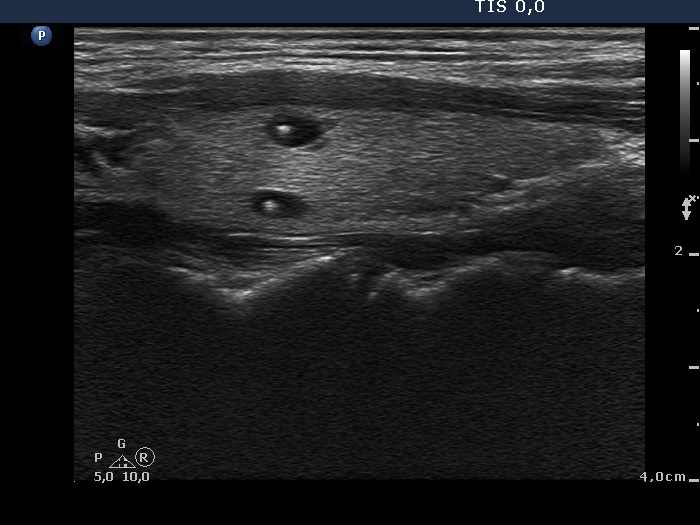

Intact thyroid with cystically dilated macrofolliculi (histological diagnosis) - case 1539

Right lobe: there are typical comet-tail artifacts, two in the left horizontal scan and one in the right longitudinal scan. The latter presents two more cystic lesions (the lower two) in which the hyperechogenic figures have only a vestigial dorsal tail. |